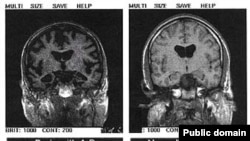

Томография мозга. Слева - болезнь Альцгеймера, справа - здоровый мозг. Но даже томография не позволяет уверенно ставить этот диагноз

В настоящее время, клинический диагноз болезни Альцгеймера ставится путем исключения других причин потери памяти и снижения интеллекта: если у человека нет инсульта, опухоли мозга или тяжелой формы алкоголизма, а память ухудшается и слабоумие прогрессирует – значит у пациента болезнь Альцгеймера. Несмотря на использование данных компьютерной и магнитно-резонансной томографии, электоэнцефалографического и биохимического исследований клинический диагноз не является совершенно точным, и окончательный диагноз устанавливается после вскрытия мозга уже после смерти пациента.